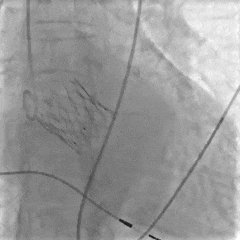

大弯侧0位,形态可见压缩

小弯侧深度尚可

瓣膜脱钩,轻微自同轴

脱钩后造影,瓣膜稳定,无反流

左侧位造影,小弯侧深度尚可